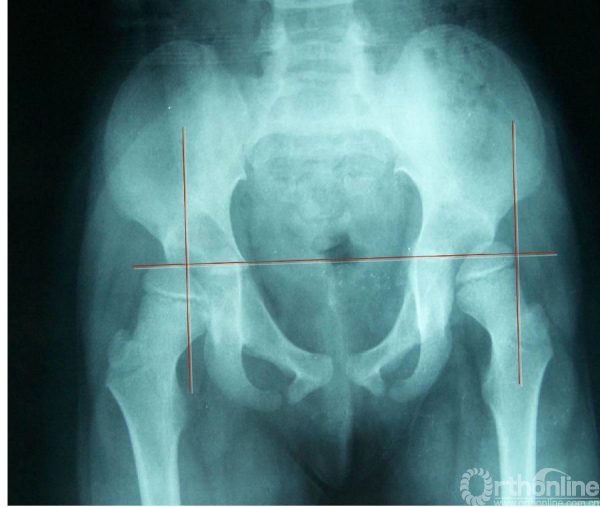

Perkin方格

连接两侧髋臼“Y”形软骨作一水平线,再自髋臼顶外缘作一垂线。此二线将髋臼分为四个象限,正常股骨头应位于内下象限。新生儿和婴儿股骨头骨骺尚未出现时,可观察股骨上干骺端的角形突起(股骨颈喙突)与Perkin线的关系。如股骨颈喙突位于外下或外上象限时,即可诊断为先天性髋关节半脱位或全脱位。脱位侧骨化中心常较小。

双髋关节半脱位